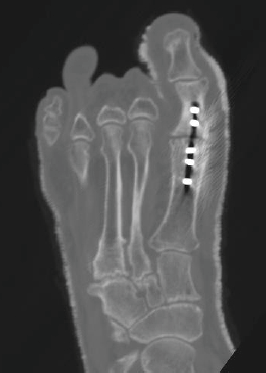

A computed tomography (CT) scan is also beneficial in determining the extent of bone healing across the fusion site but even this has its limitations. The presence of hardware and artifact make it difficult to evaluate the union site adequately in CT scans. The thickness, density, size and shape of the metal hardware also affect the quality of information that one can derive from a CT scan. Fortunately, promising new research suggests that imaging techniques such as specific and sensitive bone density scans, 3D CT reconstructions and transcutaneous ultrasound could enable physicians to diagnose non-unions at a much earlier stage, justifying the use of interventional methods sooner than physicians have traditionally practiced in the past.3